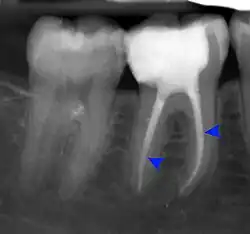

- Radiographs utilized to find dental caries and bone loss laterally or at the apex.

Decay (green) with apical abscess (blue) -